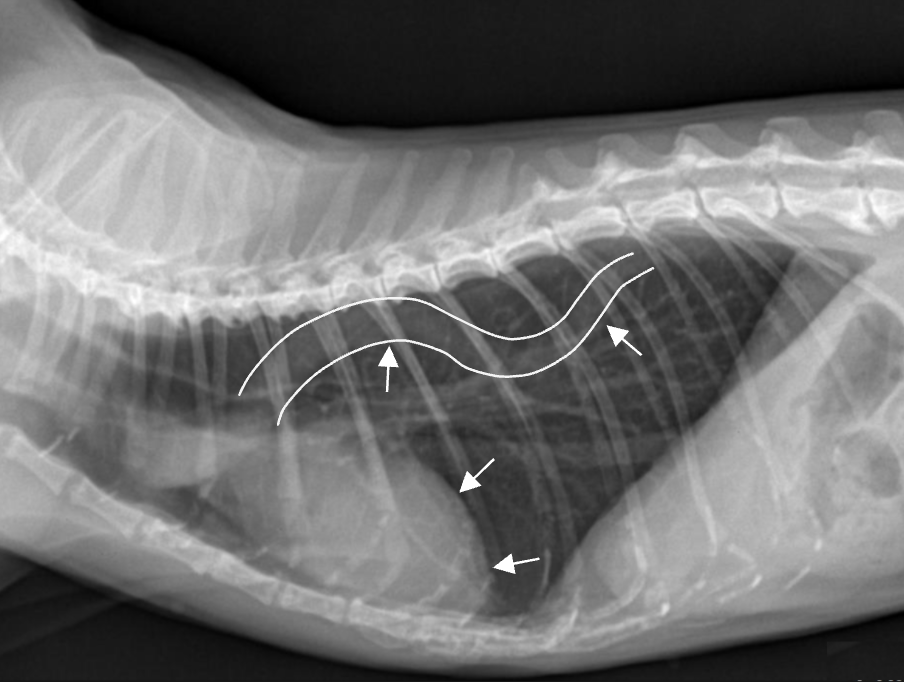

Knob sign ![]() - ๋์ด ๋ง์ ๊ณ ์์ด์์ ๋๋๋งฅ์ด ๊ตฌ๋ถํด์ง๊ณ , ์ฌ์ฅ์ด ๋์. |